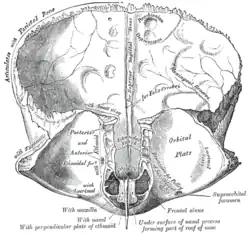

Left parietal bone. Inner surface.

Frontal bone. Inner surface.